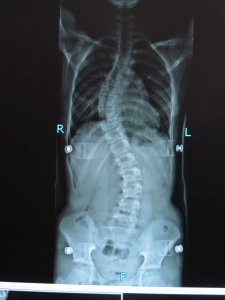

Scoliose is voor velen een vreemd, onbekend woord. Toch komt scoliose regelmatig voor. In Nederland zijn ca. 60.000 scoliosepatiënten en elk jaar komen daar ongeveer 1000 nieuwe gevallen bij. Van elke duizend mensen hebben er 40 scoliose, van wie vier in ernstige mate. Scoliose, wat is dat? Scoliose is een driedimensionale zijdelingse verkromming van de wervelkolom (ruggengraat). Kort gezegd: een kromme rug. De wervelkolom kan naar één kant kromgroeien, waardoor er één bocht ontstaat, maar meestal zijn er twee bochten. Daarnaast draait bij scoliose de wervelkolom om haar as. De verdraaiing van de wervelkolom veroorzaakt op borsthoogte aan de rugzijde een bolling van de ribben. Die bolling wordt gibbus genoemd. Wanneer en waardoor ontstaat een scoliose? Scoliose is soms al bij de geboorte aanwezig, maar openbaart zich meestal tijdens de groei van baby naar volwassene, vaak rond de leeftijd van tien jaar. De oorzaak kan liggen in afwijkingen van het bot, de zenuwen, de spieren of het bindweefsel. In 80% van de gevallen is de oorzaak van een scoliose die onstaat tijdens de groei echter onbekend. Een scoliose kan ook pas op latere leeftijd ontstaan. Vaak is dit een gevolg van het verouderingsproces. Wat houdt het hebben van een scoliose in? Scoliose heeft een bewegingsbeperking van de wervelkolom en mogelijk een beperking van de longwerking tot gevolg. Op latere leeftijd kan scoliose ook leiden tot pijn en vermoeidheid. Is de scoliose op latere leeftijd ontstaan dan geeft dit vaak veel pijnklachten en bewegingsbeperkingen. grote impact hebben op het dagelijks leven en de sociaal-maatschappelijke ontwikkeling van een individu en zijn/haar omgeving. Behandeling Scoliose is een driedimensionale zijdelingse verkromming van de wervelkolom. Er zijn in Nederland ca. 60.000 scoliosepatiënten; ca 6.500 patiënten worden per jaar in een ziekenhuis behandeld en velen buiten het ziekenhuis. Er worden jaarlijks 550 - 600 scolioseoperaties verricht. Jaarlijks komen er ca. 1.000 nieuwe patiënten bij, veelal zijn dat meisjes in de leeftijdsgroep 10-18 jaar. Hoe eerder een scoliose wordt ontdekt, des te beter kan het resultaat van de behandeling zijn. De behandeling is er in de eerste plaats op gericht verdere verkromming van de wervelkolom tot stilstand te brengen door middel van conservatieve behandeling (bijvoorbeeld oefentherapie en behandeling met een brace). Vaak duurt de behandeling een aantal jaren. Indien de scoliose daartoe aanleiding geeft dient een ingrijpende operatie plaats te vinden waarbij de wervelkolom met schroeven en staven wordt gecorrigeerd en gefixeerd.